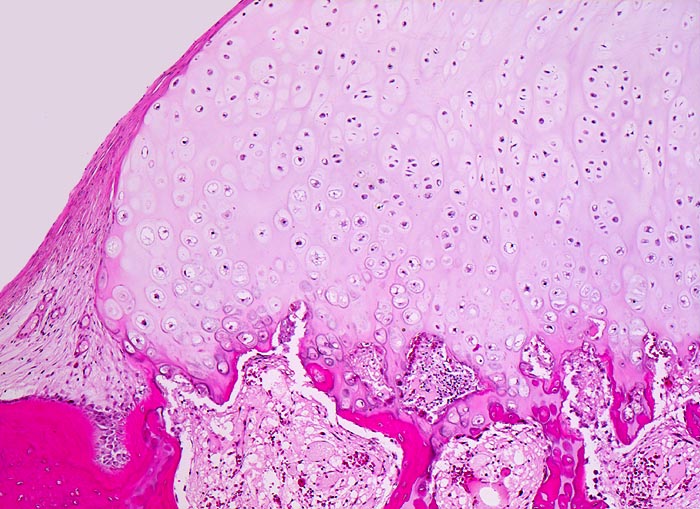

Osteochondrome sind breitbasig dem Knochen aufsitzende oder gestielte knöcherne Tumoren, die von einer 1-6mm dicken Kappe aus hyalinem Knorpel bedeckt werden. Zwischen Knorpel und Knochen liegt eine Zone enchondraler Ossifikation, die der normalen Wachstumsfuge ähnelt und den Ausgangspunkt für die Grössenzunahme des Tumors bei noch nicht abgeschlossenem Skelettwachstum darstellt. Der hyaline Knorpel wirkt etwas unorganisiert und ist bedeckt von einer dünnen Schicht Perichondrium.

• Kappenförmiges hyalines Knorpelgewebe ohne Zellatypien sitzt auf einem knöchernen Stiel. Die Knorpelkappe ist 2mm dick.

• Knorpelkappe bedeckt von einem schmalen Saum zellarmen Bindegewebes (=Perichondrium).

• Übergang des Knorpels in enchondrale Ossifikationszone wie in einer Epiphysenfuge: Knochen wird abgelagert entlang von linearen Knorpelsäulen.